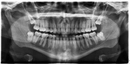

Diş hekimleri kök kalma riskini azaltmak için öncelikle detaylı radyografik incelemeler (panoramik röntgen, 3D tomografi) yaparak diş ve kök yapısını değerlendirir. Özellikle kırılgan, çürük veya şekli bozuk dişlerde dikkatli cerrahi teknikler uygularlar. Deneyimli hekimler, minimal travma prensibiyle çalışarak dişi bütün halinde çıkarmaya özen gösterirler.

Kök kaldığında tedavi kompleksite seviyesi; kökün boyutu, konumu, enfeksyon varlığı ve hastanın genel sağlık durumuna göre değişir. Küçük, asemptomatik kökler bazen takip edilebilirken, çoğunlukla cerrahi müdahale gerekir. Bu işlem normal çekimden daha detaylı olup lokal anestezi altında diş eti kesisi ve kemikte küçük bir pencere açılmasını içerebilir.